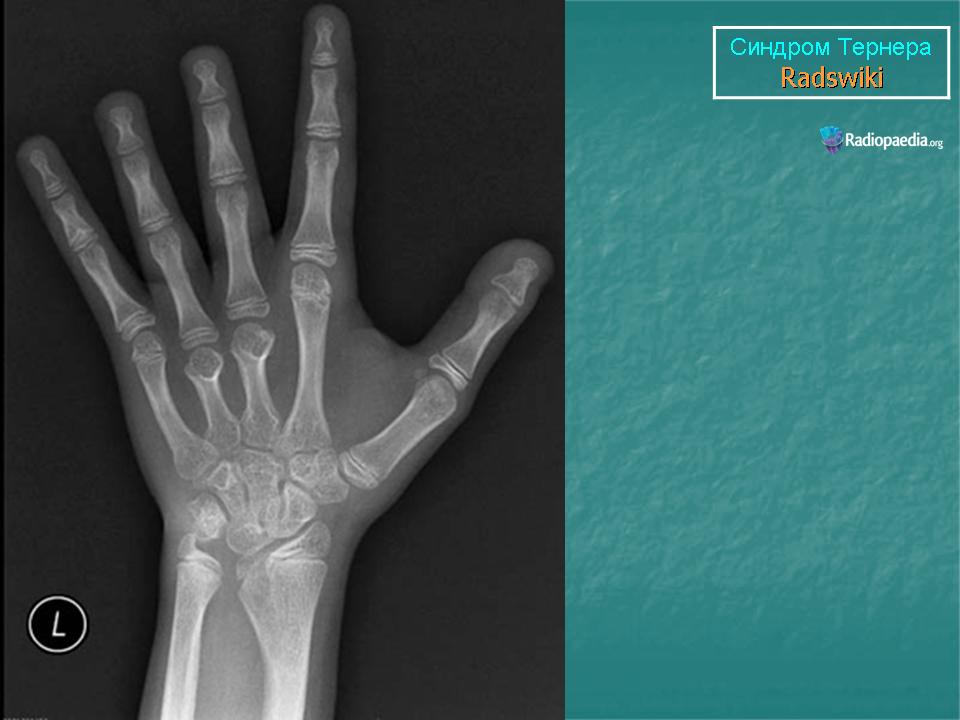

Тернера синдром. Пнд, 15/01/2018 - 23:08 #1 Катенёв Валенти... Не на сайте Был на сайте: 7 лет 3 месяцев назад Зарегистрирован: 22.03.2008 - 22:15 Публикации: 54876 http://24radiology.ru/vizualizatsiya-malogo-taza/sindrom-ternera/

http://24radiology.ru/vizualizatsiya-malogo-taza/sindrom-ternera/